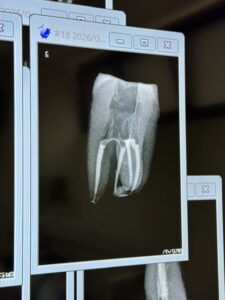

M先生

前日に二人でw水炊き屋に行ったM先生。

彼のテストケースは以下だ。

パフもあり、上手い!

先生も教わる方でなく、技術を人に伝え伝承していく側の人間だ。